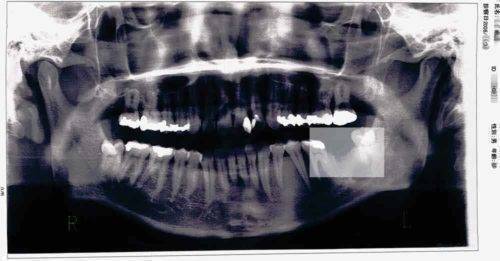

さて、こちらの画像をご覧あれ。

いきなりグロいですかね(笑

虫歯の治療だらけの汚いレントゲン画像ですみません。これが30代半ばのときのキノコ隊長の歯です。Lの字が薄いですが、左の奥歯のところがすっぽり抜けてます。まぁまぁ、虫歯を放置すると年齢関係なくこうなる可能性があるということですね。

ちなみに詰めものが取れた歯は、上のレントゲン画像の抜いた奥歯の左隣の6番の歯です。

そんな左下7番の奥歯を抜歯したあとのレントゲン画像がこちら・・

抜歯した7番を中心に根尖病巣による膿で、歯槽骨が解けているのがわかるかもしれません。6番と8番の歯の影が他とはちょっと違うようにみえるのではないでしょうか。それでも、これだと歯槽骨を溶かしていたということに疑問を抱く方もおりますかね。

そこで、もう一枚みてもらいましょう。